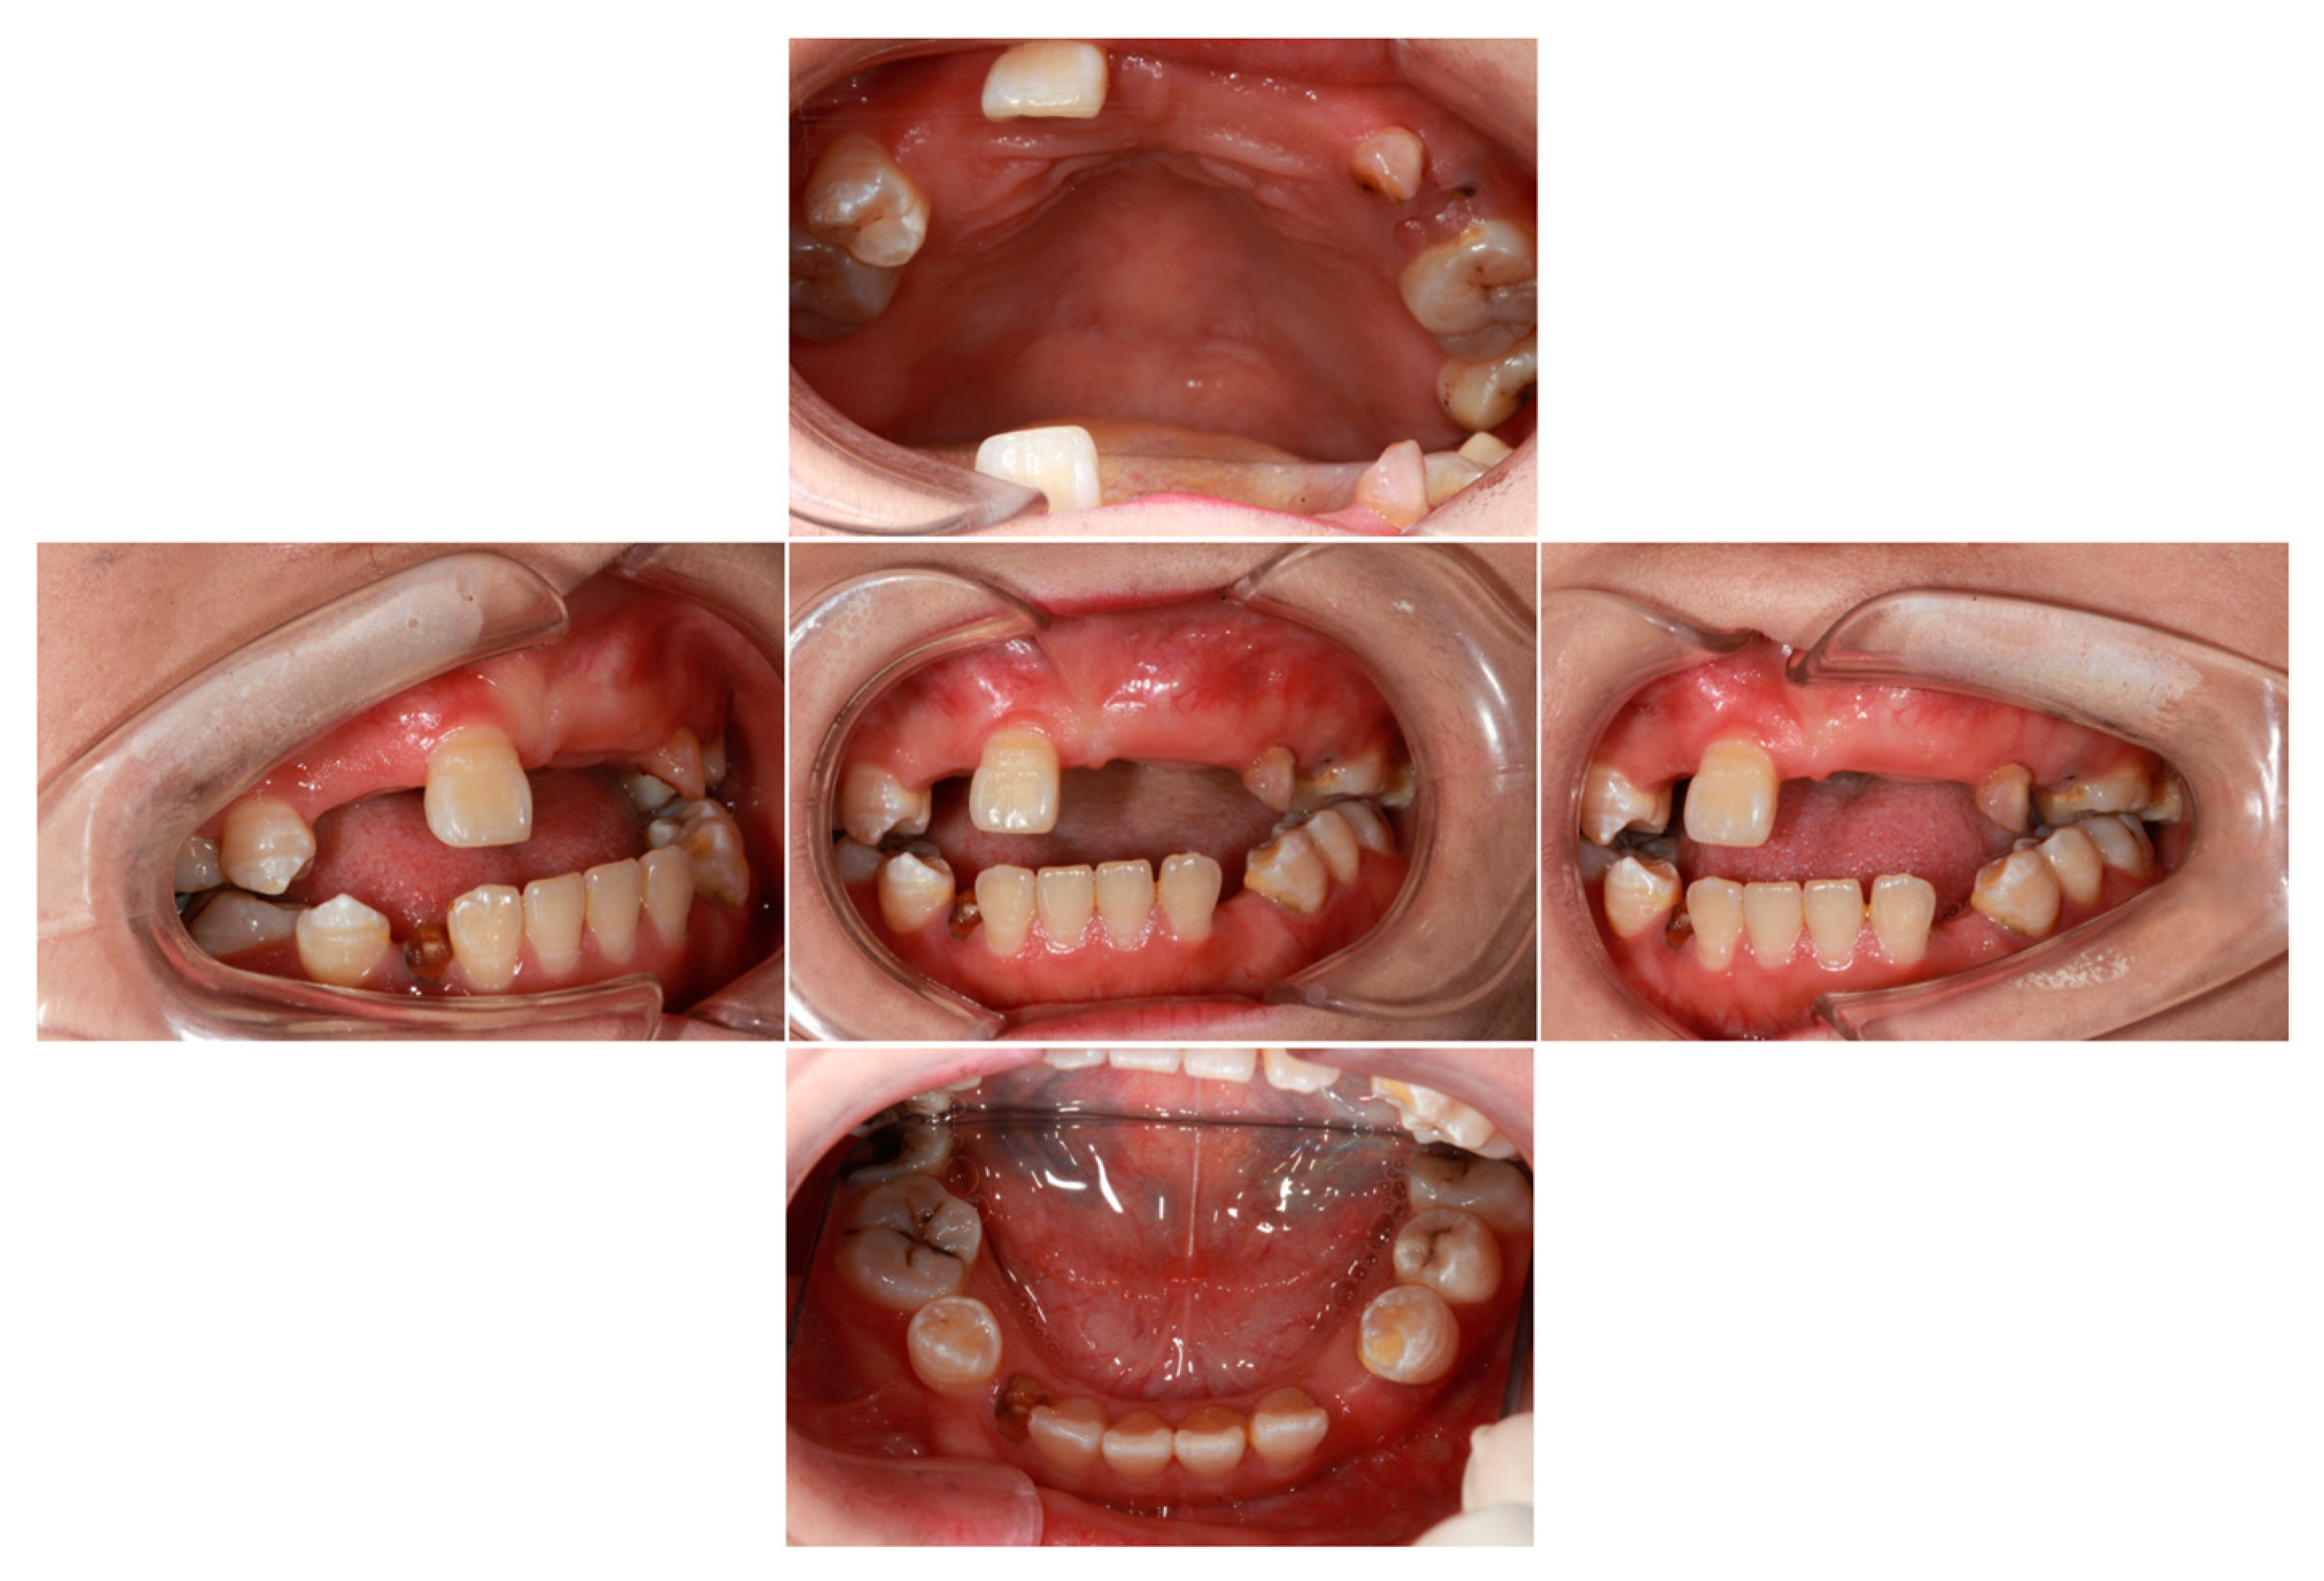

2.1. Clinical Features of Proband

4.1. Case Presentation